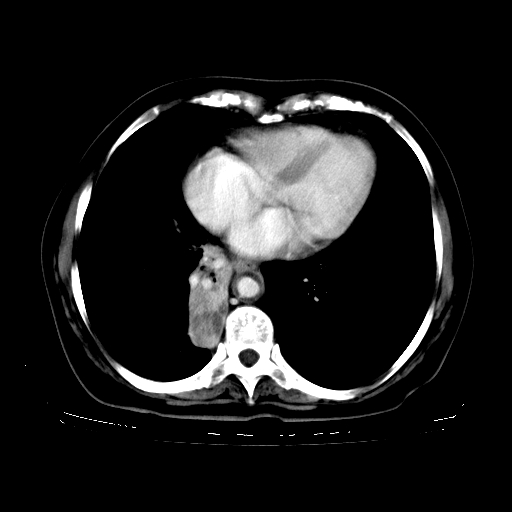

女,70岁,咳嗽、咳痰一个月,低热一周。

1.左上肺结核,部分纤维化。右肺中下叶部分肺不张,内见液化、坏死及点状钙化,右中下叶支气管壁增厚、管腔狭窄,见多个点状钙化,结合临床考虑支气管内膜结核,建议痰检查抗酸杆菌并参考血沉。两肺多个小圆点状高密度灶,境界模糊,多考虑结核肺内播散。但本人年龄较大首先应支气管镜检以除外右肺癌。

2.胸主动脉夹层。

支持,首先一元论解释。胸主动脉部分层面环形低密度,中心强化。环形影不强化。不象真假腔的改变。我考虑动脉炎,不太支持夹层动脉瘤-和大家的观点不一致,希望楼主让患者再做个心血管的彩超吧。